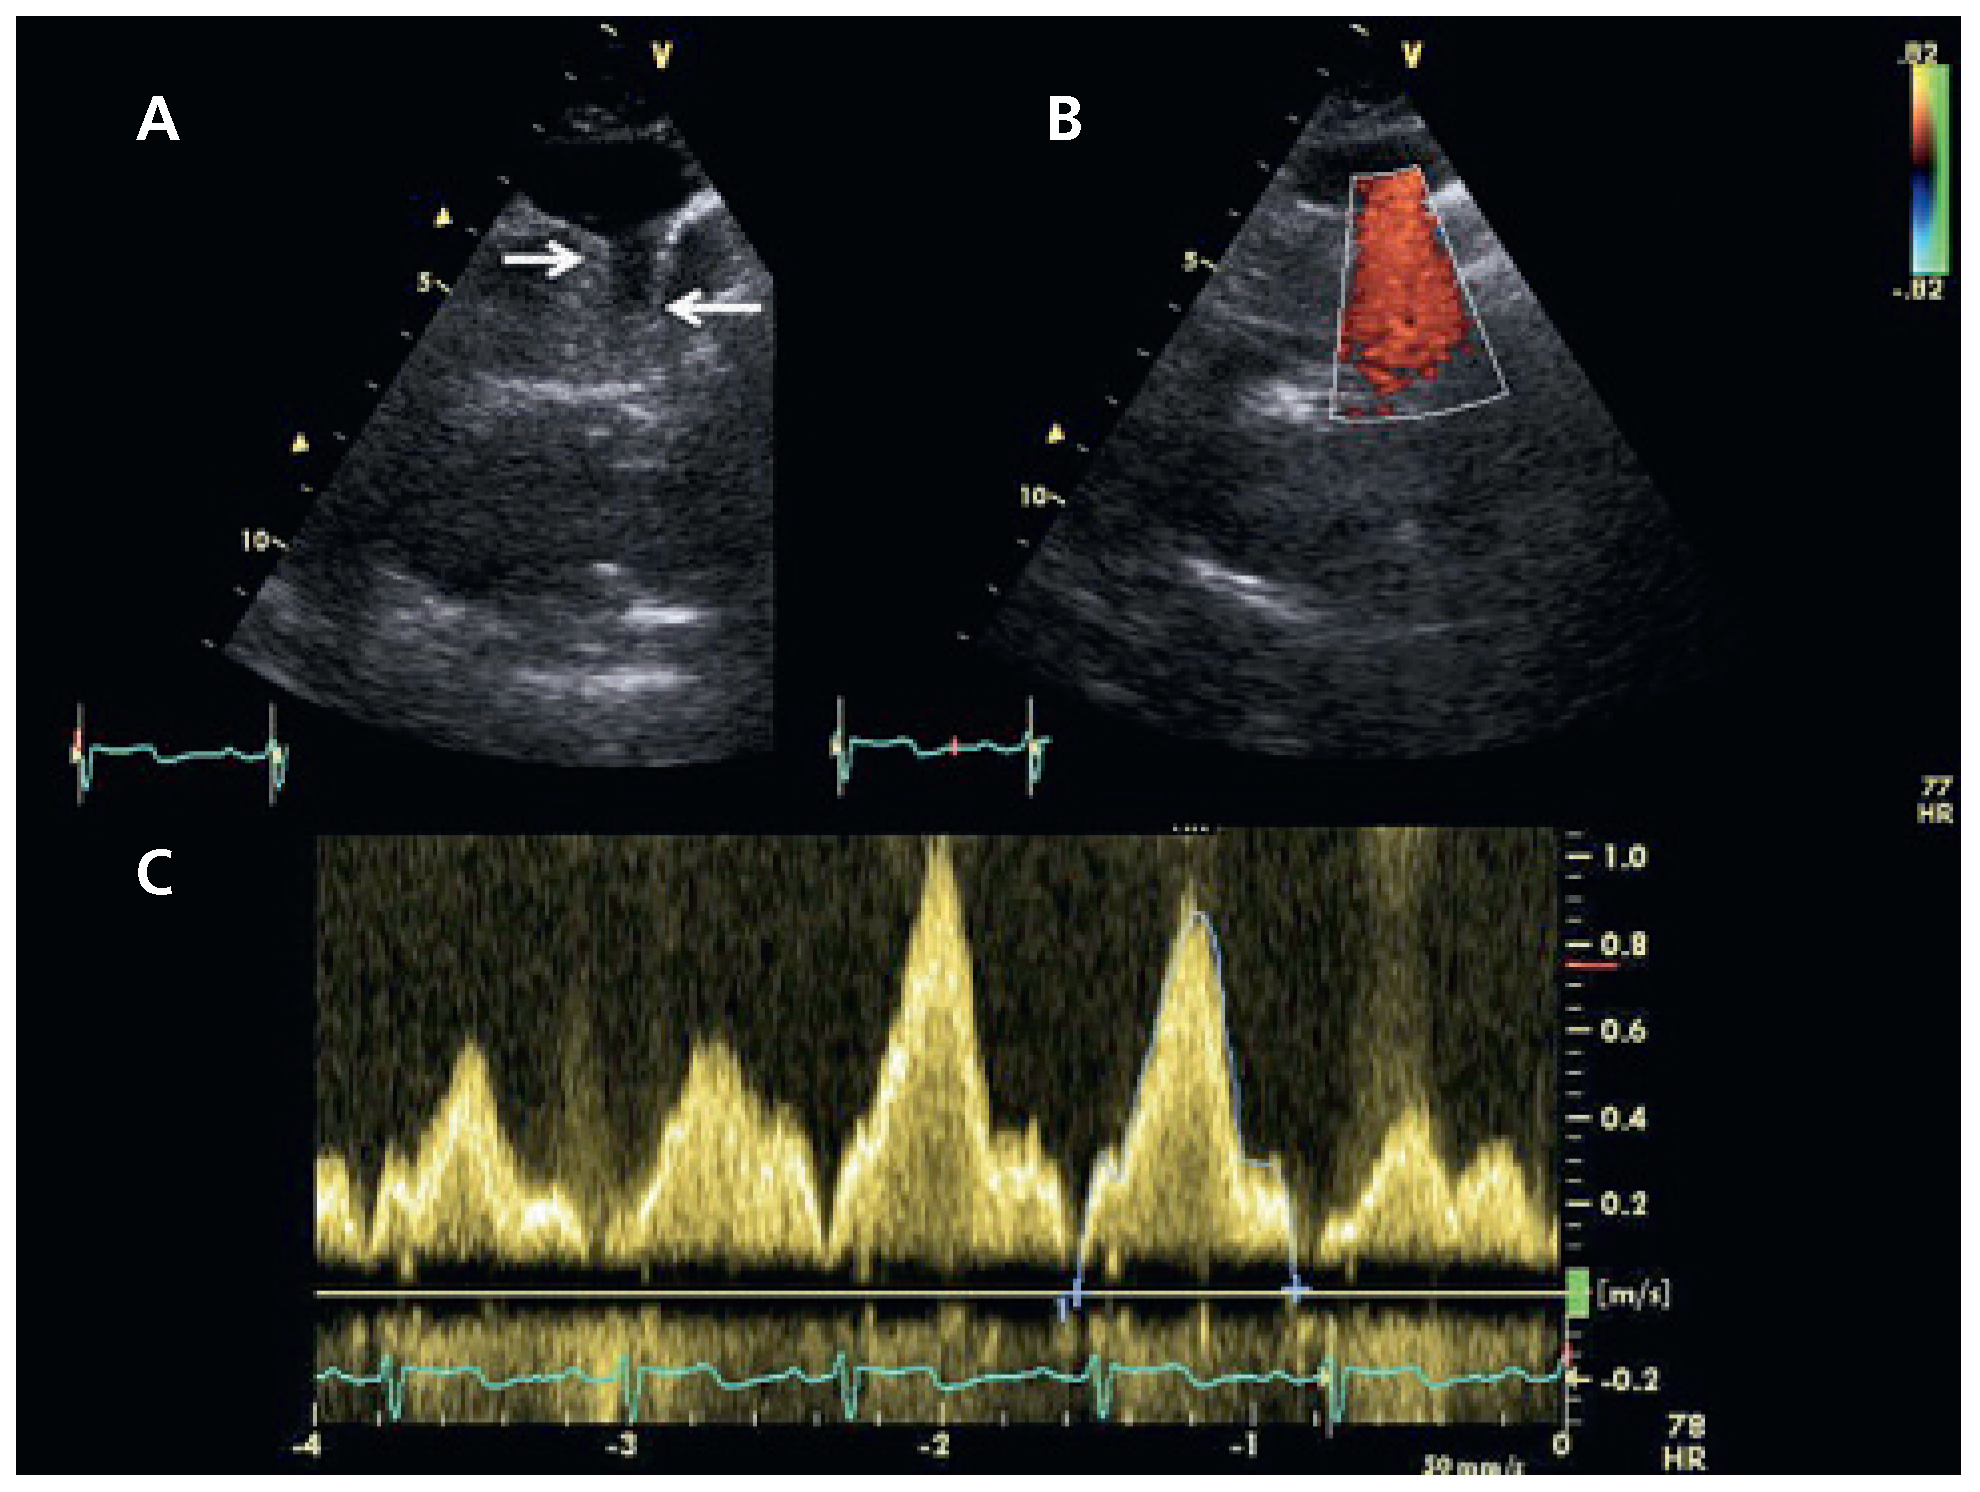

Un complément d’échocardiographie transthoracique est réalisé, permettant de visualiser le retour veineux anormal dans la veine innominée par une vue sus-sternale modifiée (Figure 3). A nouveau, un examen attentif du septum interauriculaire en apical 4 cavités et en sous-costal ne montre pas de communication inter-auriculaire (CIA) associée. Nous n’avons pas jugé utile de compléter les investigations par un examen trans-œsophagien en raison de l’état général précaire de la patiente et de l’absence de sanction thérapeutique.

Figure 3. A Vue sus-sternale modifiée montrant l’abouchement d’un vaisseau dans la veine innominée (flèches). B Le Doppler couleur confirme un drainage dans la veine innominée et non une veine cave supérieure gauche se drainant dans le sinus coronaire. C Flux continu au Doppler pulsé confirmant la nature veineuse du flux.